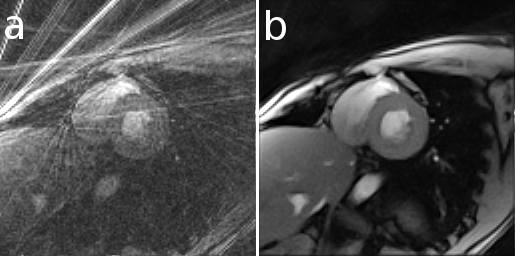

Example showing differences between filtered backprojection (right half) and iterative reconstruction method (left half)

Here is an example that illustrates the benefits of iterative image reconstruction for cardiac MRI.[19]